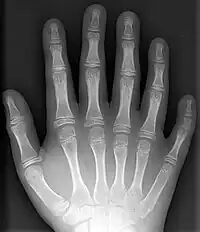

El ser humano tiene cinco dedos en cada mano y reciben el nombre de pulgar (o dedo gordo de la mano o primer dedo de la mano), índice (o segundo dedo de la mano), medio (o tercer dedo de la mano, o dedo corazón, o dedo cordial o dedo mayor), anular (o cuarto dedo de la mano) y meñique (o quinto dedo de la mano o dedo auricular).

Los huesos de los dedos se llaman «falanges». Cada dedo posee tres, excepto los pulgares y dedos gordos del pie, donde hay solamente dos. La falange proximal de cada dedo se articula con el hueso metatarsiano correspondiente (en los pies) o hueso metacarpiano correspondiente (en las manos).